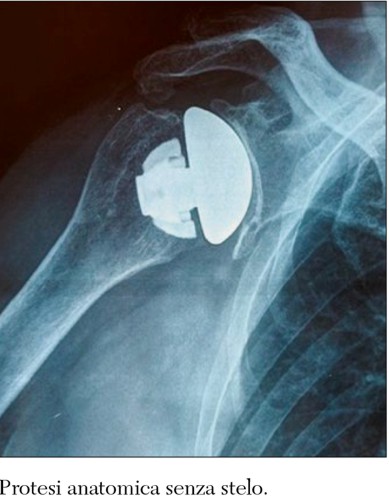

La protesi totale anatomica ha l’obiettivo di riprodurre l’anatomia della spalla normale e il requisito essenziale per il suo utilizzo è che la cuffia dei rotatori sia integra e funzionante. In questo tipo di protesi la testa omerale si sostituisce con una cupola metallica e la superficie glenoidea si sostituisce con una componente concava in polietilene.

Le protesi senza stelo hanno il vantaggio di adattarsi alla struttura anatomica del paziente anche nei casi di dismorfismo sia esso degenerativo che postfratturativo. Inoltre tale impianto riduce il rischio di gravi complicanze quali le fratture periprotesiche e l’instabilità articolare. Infine, l’utilizzo di questo tipo di protesi di spalla facilita l’eventuale intervento di revisione.

L’utilizzo delle protesi di spalla è sempre più diffuso con buoni risultati a breve e medio termine. La disponibilità di protesi senza stelo o con steli corti ha facilitato e implementato il loro utilizzo in quanto tali impianti sono più facili da applicare con un minore impegno chirurgico. Inoltre la letteratura mostra che i risultati delle protesi di spalla senza stelo sono sovrapponibili a quelli delle protesi tradizionali e che queste sono anche migliori dopo intervento di revisione protesica.